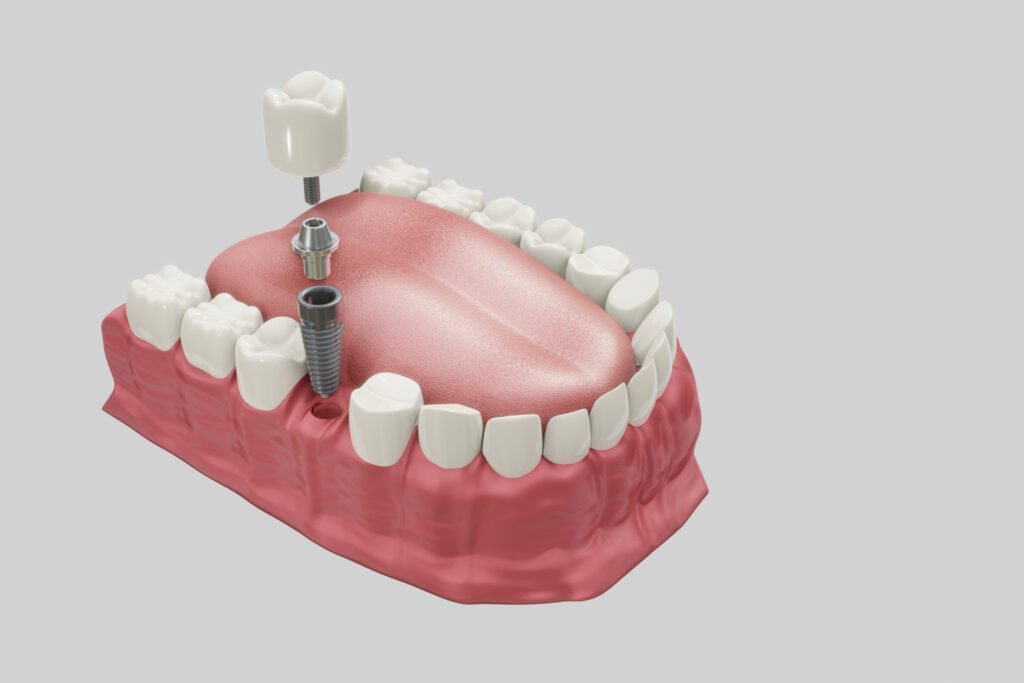

インプラント治療に対する考え方

当院ではインプラント治療は行っておりません。

インプラント治療が最善策と判断された場合や、患者様がインプラント治療をご希望される場合は、インプラント治療専門の信頼する医療機関をご紹介いたします。